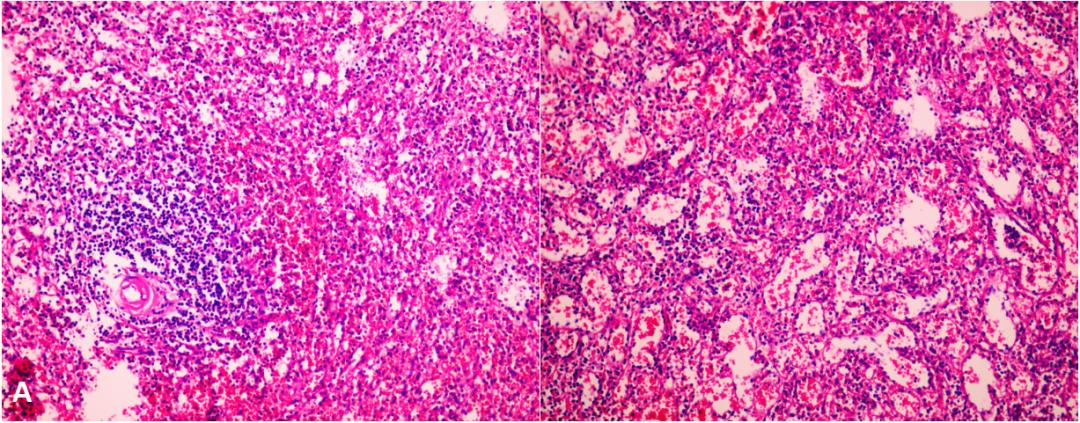

图3. 脾脏病理:慢性淤血性脾肿大

对于自发性脾-肾静脉分流患者,经颈静脉肝内门体分流术(TIPS)联合脾肾分流栓塞术是一种可行的方法,但肝性脑病是TIPS术后的一大重要并发症。该患者反复出现肝性脑病,三系降低且巨大脾脏压迫胃肠道引起相应消化道症状,故而考虑手术切除脾脏,同时阻断脾肾分流。与患者及其家属沟通后,2023-06-27于我院普通外科 行“脾切除术、脾-肾分流断流术” ,术中见肝脏体积缩小,肝表面欠光滑,呈结节样硬化改变,脾脏增大,长径约16.0 cm,脾门血管明显增粗、迂曲,其中脾动脉直径约0.8 cm,脾门曲张静脉直径约1.2~1.6 cm,呈“蚯蚓状”迂曲分布与脾门区域,行脾切除、同时阻断脾肾静脉分流。术前患者血*水氨**平在100 umol/L左右波动,术后6天查血*水氨**平降至正常范围。术后予以护胃、保肝、纠正低蛋白、雾化祛痰、预防血栓、输注血浆及适当补液等治疗后好转出院。